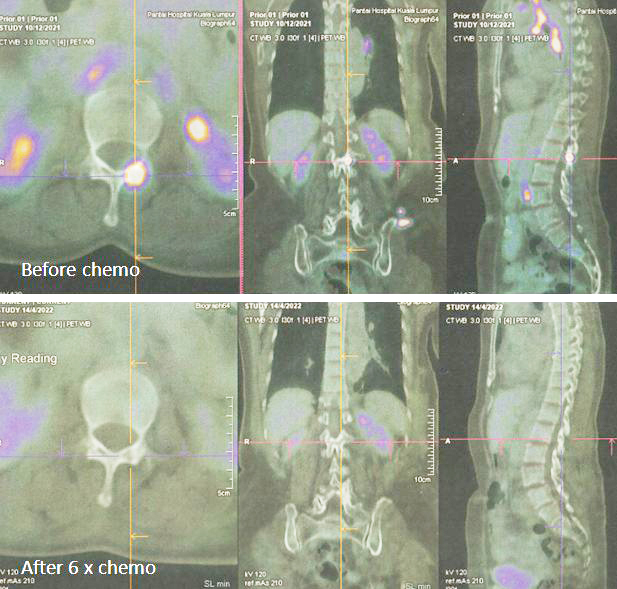

Karena metastasis seperti yang ditunjukkan pada pemindaian PET yang dilakukan pada 10 Desember 2021, Lucy tidak punya pilihan selain melanjutkan kemoterapi. Memang kanker telah menyebar luas.

8. Pemindaian PET pada 14 April 2022 memang menunjukkan respon yang baik.

Sebelum kemo ———– setelah 6 siklus kemo

1. Temuan scan menunjukkan respon metabolik lengkap pada kekambuhan dinding dada, metastasis nodal dan penyebaran jauh.

2. Perubahan atelektasis baru pada dasar paru kiri dengan efusi pleura kiri ringan mungkin disebabkan oleh infeksi baru-baru ini.

1. Hasil kemoterapi yang luar biasa.

Bandingkan ketiga gambar ini :

Kiri: Setelah operasi Lucy menjalani terapi alternatif, menolak kemoterapi. Hasilnya adalah metastasis luas (tengah).

Kanan: Lucy tidak punya pilihan selain menjalani kemoterapi. Hasil dari 6 siklus kemoterapi sungguh luar biasa! Selama lebih dari 25 tahun saya berurusan dengan pasien kanker, saya belum pernah melihat hasil kemoterapi yang luar biasa seperti ini. Salut dengan ahli onkologi! Anda menyelamatkan Lucy!

Faktanya, hasil chemo ini sangat sulit dipercaya sehingga orang tergoda untuk bertanya apakah itu asli dan bukan palsu? Jawaban saya TIDAK, studi detail hasil PET scan di bawah ini adalah nyata! Kaji gambar berikut dengan cermat – sebelum dan sesudah kemoterapi.